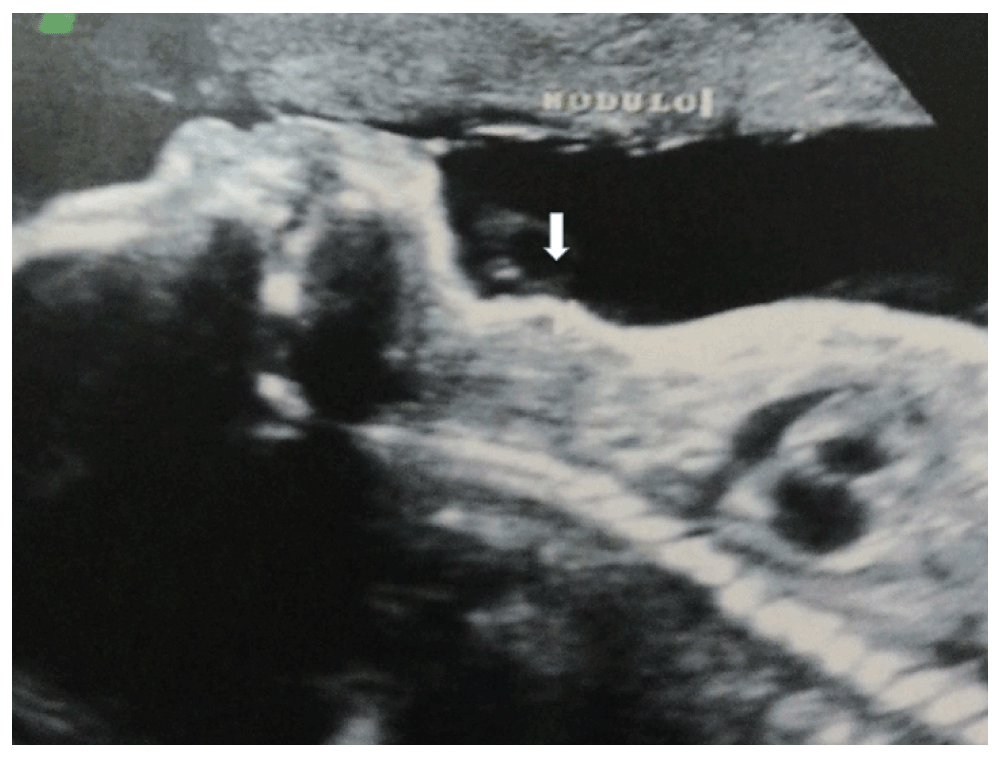

From a routine ultrasound during pregnancy, the fetus had been diagnosed with a cervical mass, considered initially to be a goiter (Figure 1) by doctors at another institution. Family history of the mother uncovered a cousin with hypothyroidism. The mother was previously healthy, but after diagnosis of the cervical mass of the fetus, she was tested for thyroid hormones and had hypothyroidism diagnosed during pregnancy (TSH: 5.0 mUI/mL – normal: 0.2 to 3.0 mUI/mL; free T4: 0.7 ng/dL – normal: 0. To 1.3 ng/dL; antithyroglobulin antibodies: 65 U/mL – normal: inferior to 60 U/mL and thyroid antiperoxidase antibodies: 166 UI/mL – normal: inferior to 9 UI/mL). Two single doses of 200µg of levothyroxine were administered into the amniotic fluid, one during the 28th and one during the 31st week of pregnancy, in order to treat the supposed fetal thyroid hormone deficiency. Chorioamnionitis appeared after the second levothyroxine administration which triggered a premature cesarean birth which was undertaken in the other hospital. The premature newborn had sepsis due to maternal infection (chorioamnionitis) and remained in mechanical ventilation for 10 days. After tracheal extubation, he remained in nasal continuous positive airway pressure (CPAPn) for 7 more days, and after that was kept on oxygen therapy for 10 days. He was discharged from the hospital 50 days after birth, still presenting with a laryngeal stridor that was attributed to tracheal malacia by the doctors that initially treated the patient.